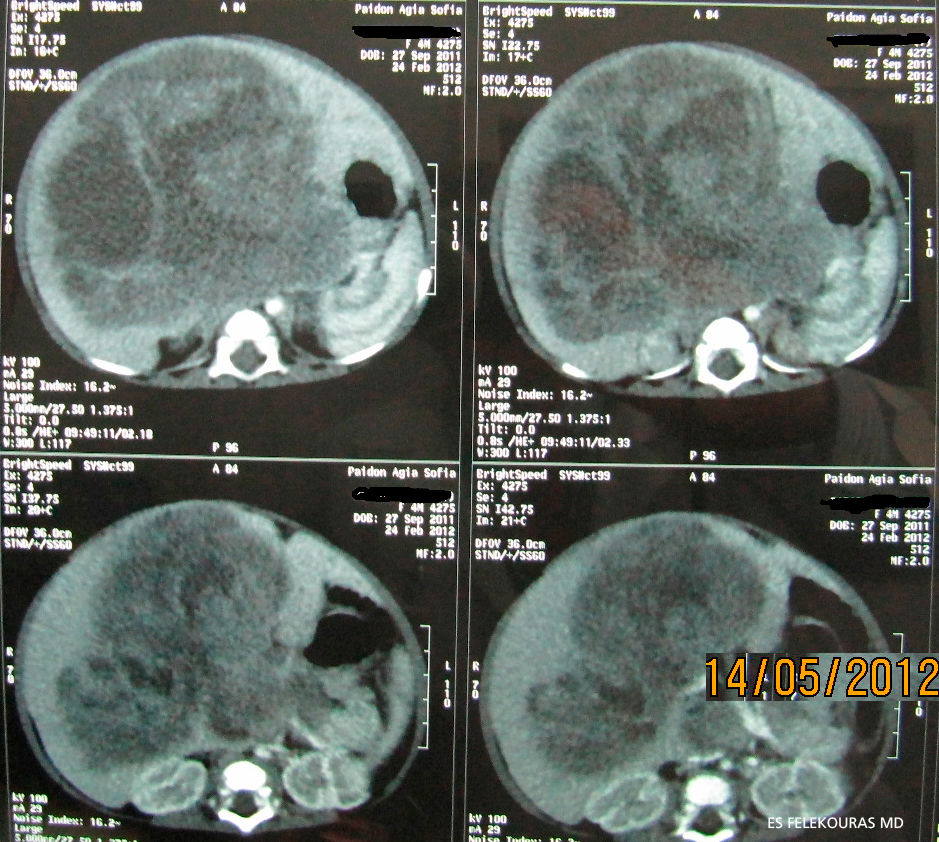

Η διάγνωση τίθεται με το US και επιβεβαιώνεται με την ΑΤ και τη MRI, με τις οποίες σχεδιάζεται το πλάνο της χειρουργικής θεραπείας, όπως και για κάθε όγκο του ήπατος. Πρέπει να τονισθεί ότι ο όγκος είναι σχετικά ανάγγειος (Εικόνα 1).